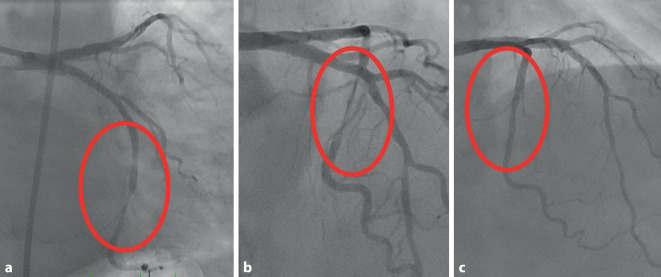

This section collects any data citations, data availability statements, or supplementary materials included in this article.